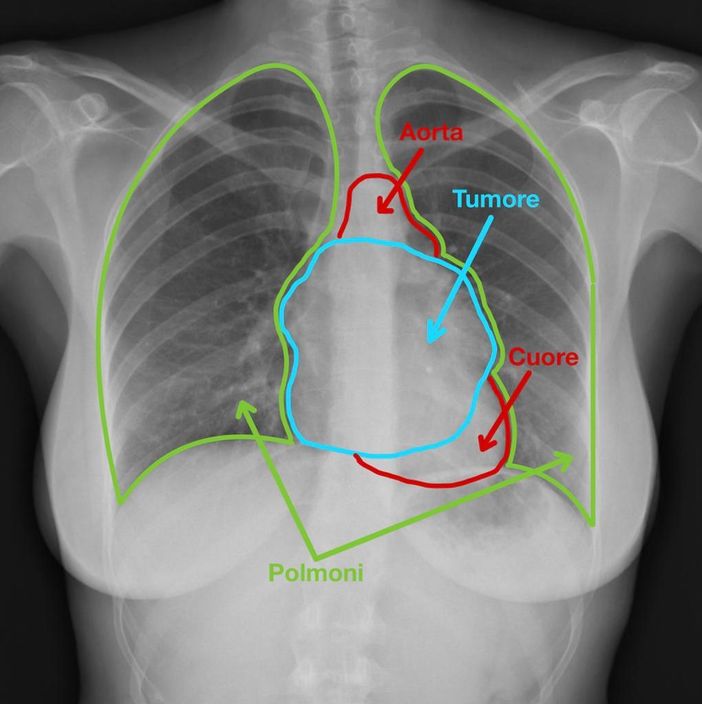

Un tumore "timico" che, con i suoi 13 centimetri, occupava gran parte del torace. Era in queste condizioni la donna di 39 anni che è stata salvata da un intervento miracoloso alle Molinette di Torino.

La sfida, in questo caso, era di riuscire ad asportare un tumore di così grandi dimensioni, localizzato sopra il cuore e l’aorta, mediante l’utilizzo del robot, guidato dal chirurgo toracico. I dottori Paraskevas Lyberis e Francesco Guerrera, della Chirurgia Toracica universitaria (diretta dal professor Enrico Ruffini), hanno utilizzato una tecnica chirurgica modificata, avvalendosi del robot, mediante l’utilizzo di nuovi traccianti fluorescenti che hanno consentito di asportare la grossa massa toracica senza lasciarne alcun residuo nè danneggiare polmoni e cuore.